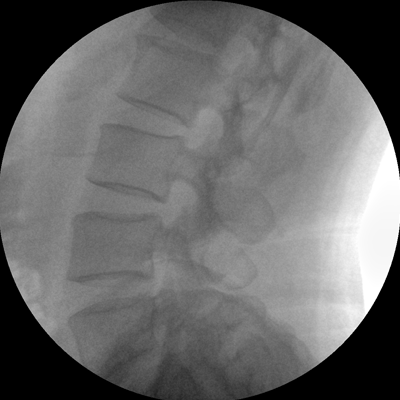

小巧輕便 超凡靈動(dòng) PLX C1116

●全數(shù)字化百萬(wàn)像素影像系統(tǒng),圖像清晰